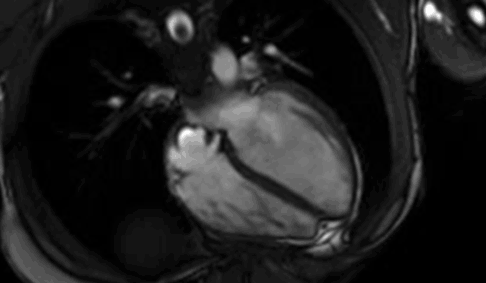

The fasting requirement is dependent on components being included in the test. Renal - Lakeview Imaging

Renal - Lakeview Imaging from www.lakeviewimaging.com.au